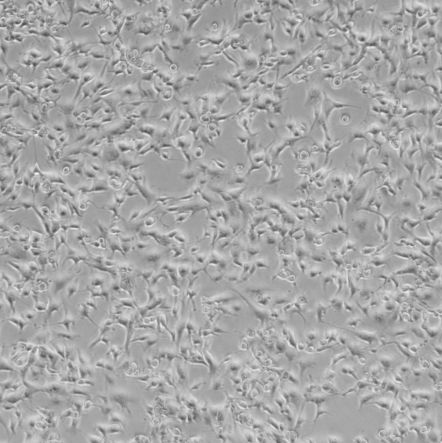

Hs 746.T_人胃癌细胞

细胞名称:Hs 746.T_人胃癌细胞

货号: SNB-TC-0323

种属来源:人

性别年龄:男性,74岁

组织来源:胃

生长特性:贴壁生长

细胞形态:上皮样

细胞规格:1 X 106cells/T25或1 mL冻存管

培养条件:DMEM + 10% fetal bovine serum (FBS)

37 ℃, 5% CO2

冻存条件:90% FBS + 10% DMSO

传代方法:1:2到1:8传代,1-2天传1代